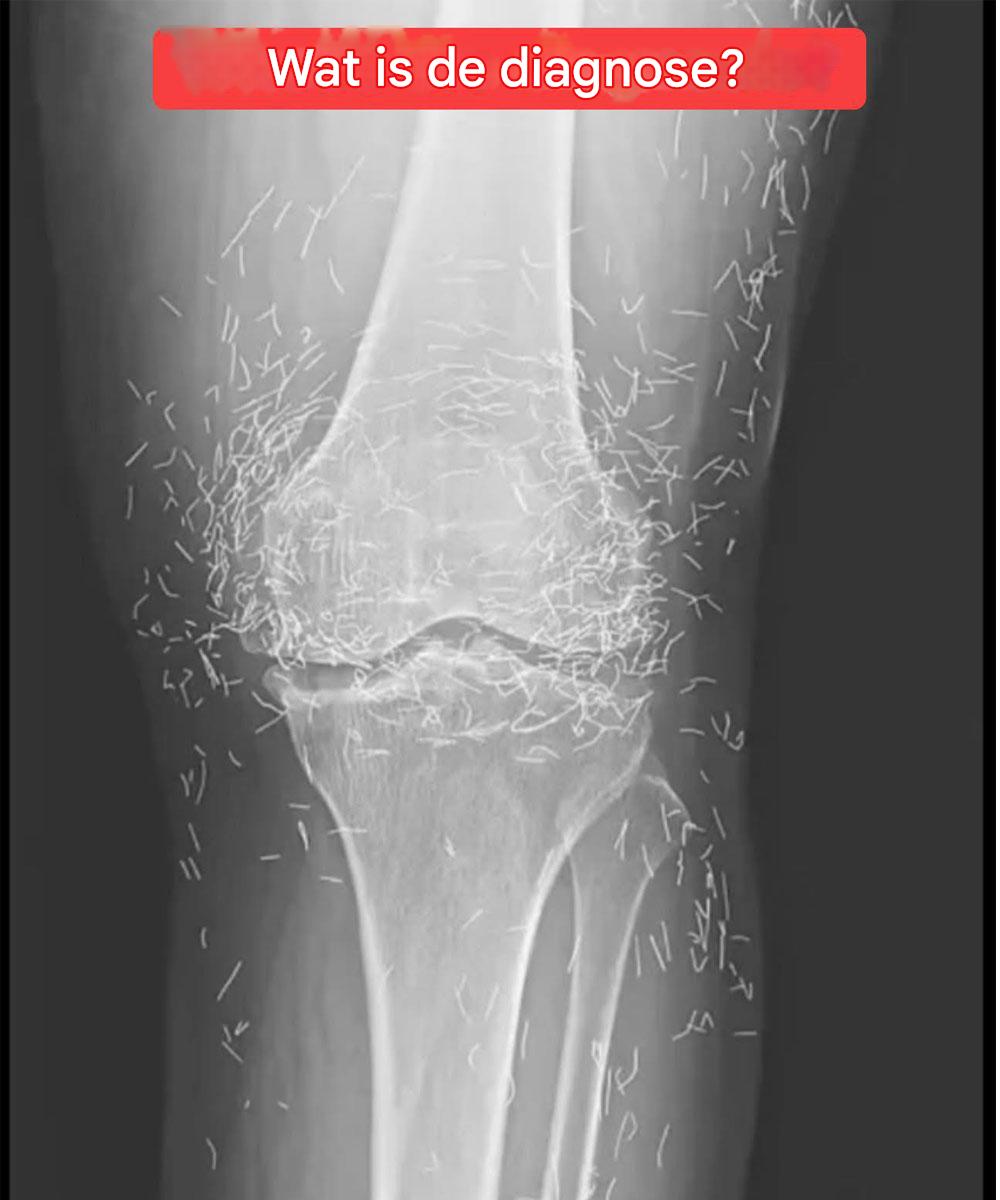

Röntgenfoto onthult honderden gouden naalden in knieën van vrouw

Toen artsen een röntgenfoto van de knieën van een oudere vrouw met ernstige gewrichtspijn onderzochten, ontdekten ze een goudmijn: honderden kleine gouden acupunctuurnaaldjes die in haar weefsel waren achtergebleven.

Het rapport stelt dat tijdens de acupunctuurbehandeling van de vrouw naalden, waarschijnlijk van goud, opzettelijk in haar weefsel waren achtergebleven om continue stimulatie te garanderen.